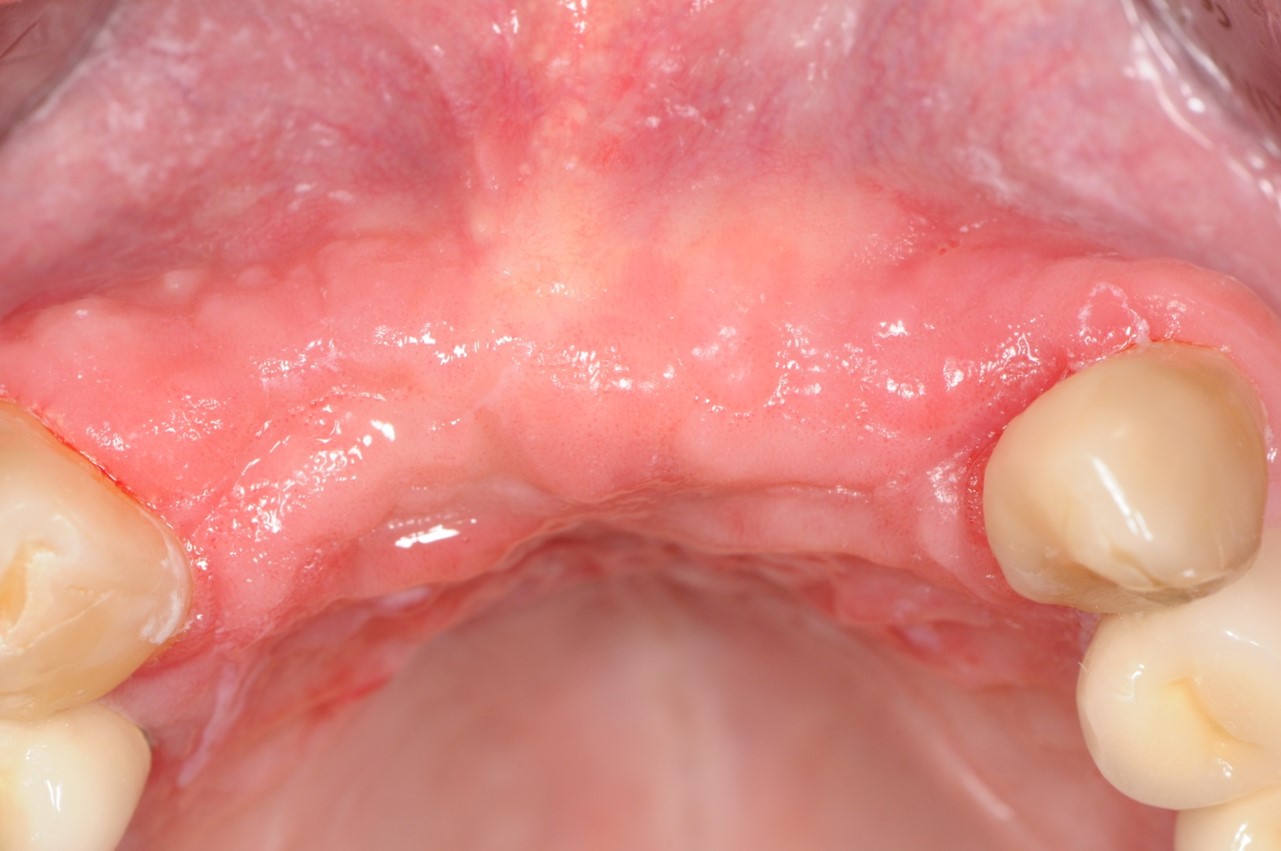

16/19 - 10 months after bone ring surgery - 2 months after re-entry

Long-term case: socket preservation and bone augmentation with two maxgraft® bonering - Dr. B. Giesenhagen